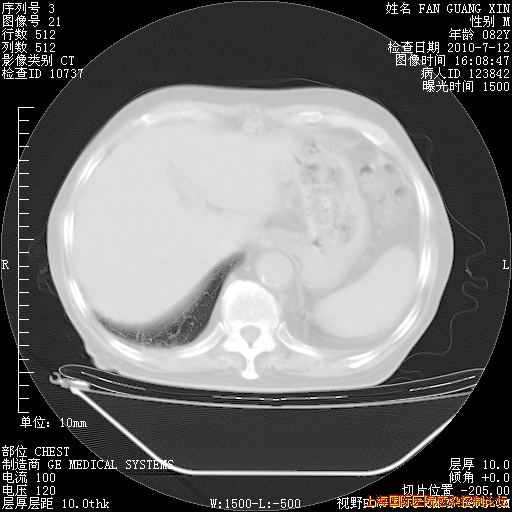

今天复查CT

今天CT

整整相隔30天的肺部CT好像有所好转啊。甲强龙减量第3天,需要观察体温。